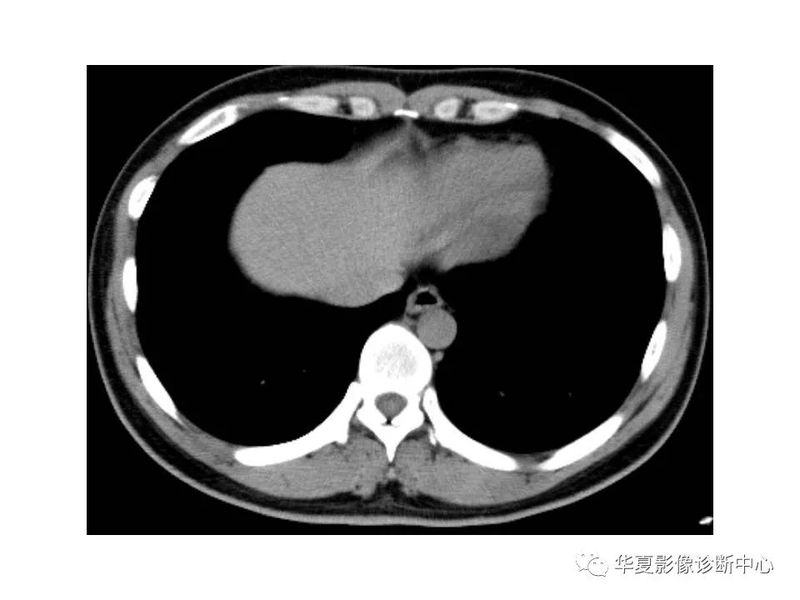

干货 | 汇总胸部CT读片扫盲知识,看懂胸部CT不再难